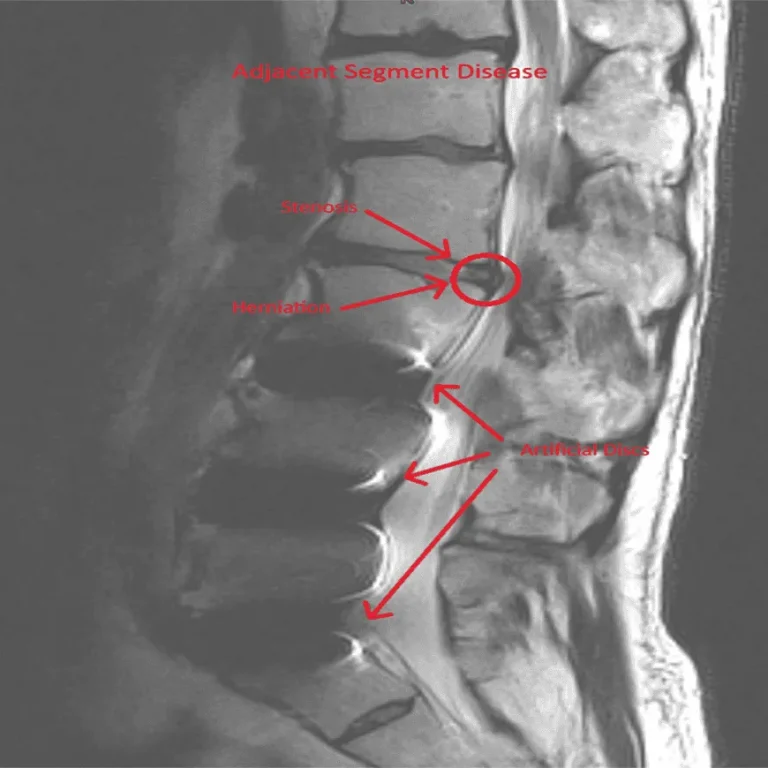

MRI image of a spine with labeled stenosis, herniation, and artificial discs.

Adjacent Segment Disease

MRI of a spine showing adjacent segment disease with labels for stenosis, herniation, and artificial discs.

Spinal instability and degeneration at levels above and below the implant.